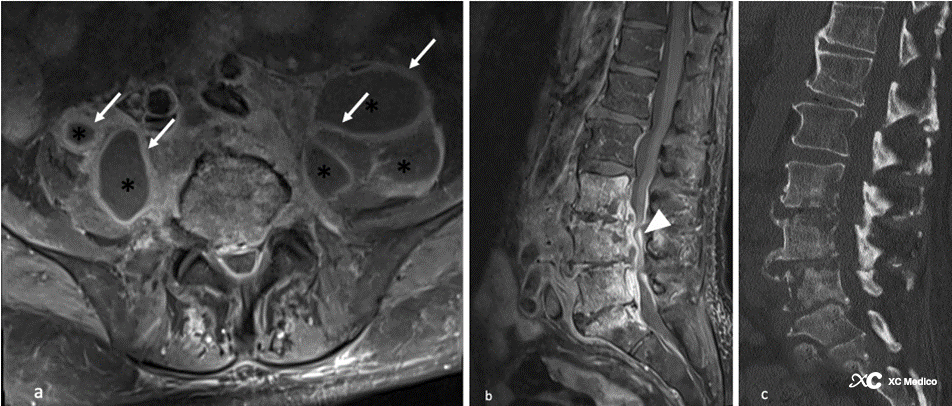

Примечания: 65-летний мужчина с (а) осевыми и (б) поясничными абсцессами (звездочками) с перегородкой и усилением стен (белые стрелки). Копанный межпозвоночный диск без значительного улучшения. Сжатие дурального мешка (белая стрелка). (C) CT Реконструкция изображения L3 до S1 Разрушение тела позвонка.